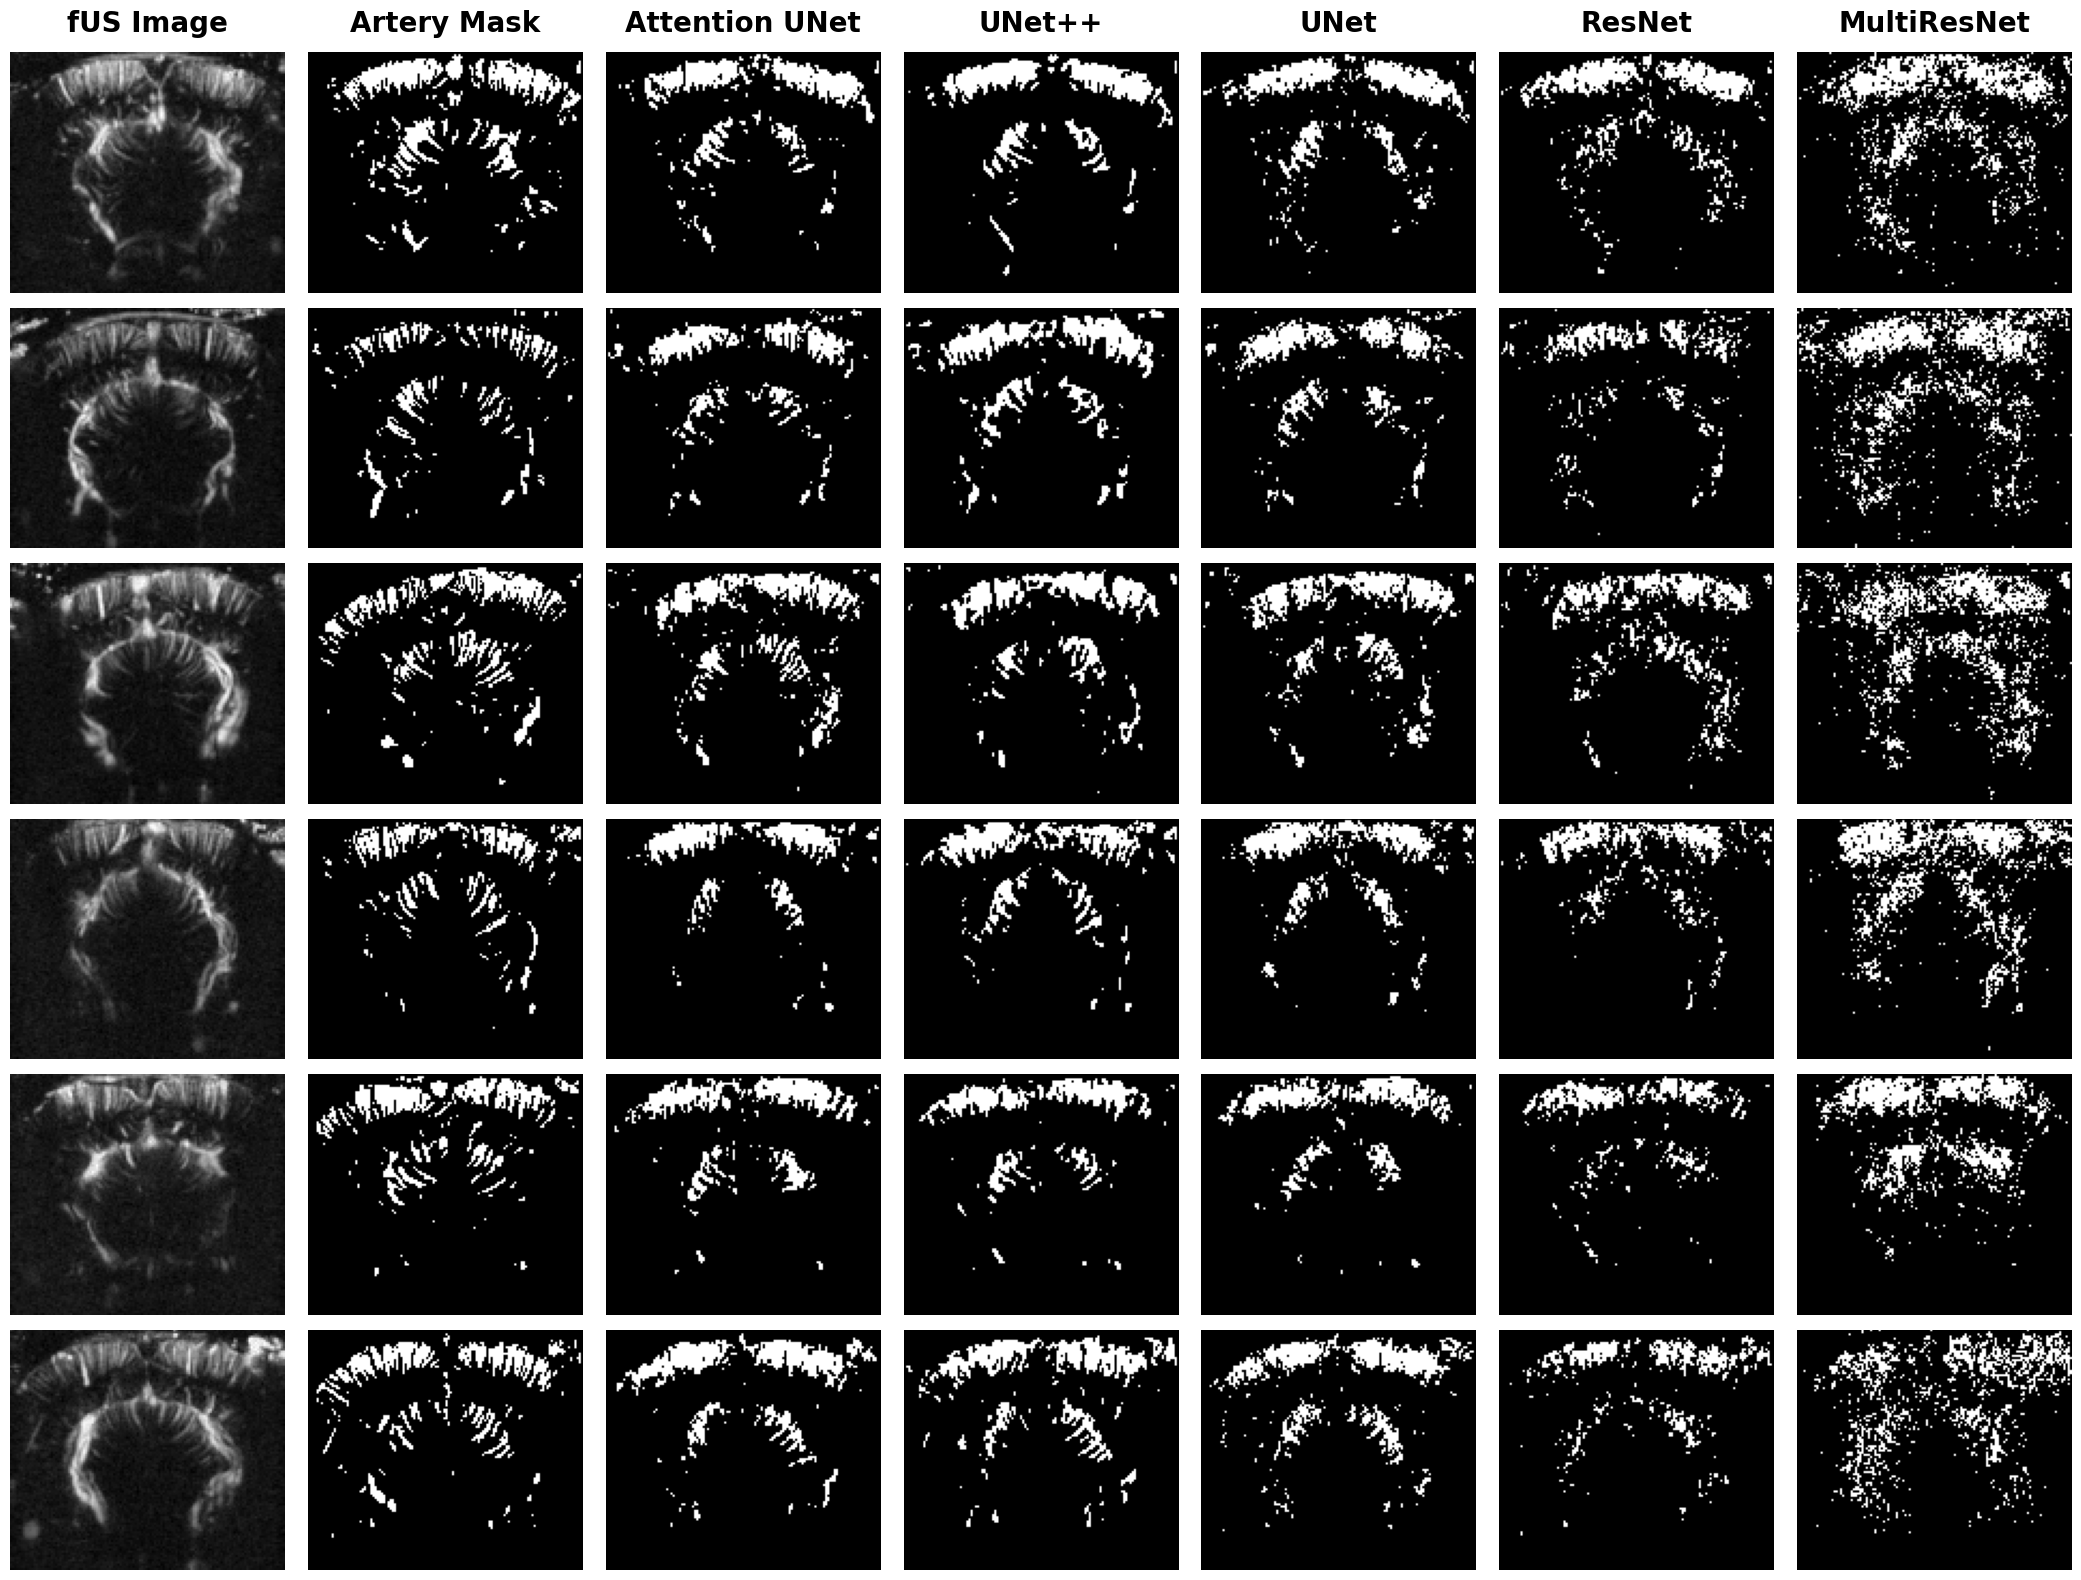

The highest performance metrics achieved were an accuracy of , an F1 Score of , and a Jaccard Index (IoU) of , aligning with results typically seen in vessel segmentation [42, 41]. The best results on average are predominantly achieved by the Attention UNet and UNet++, which seem better suited for this segmentation task due to their ability to focus on relevant regions within the image through attention mechanism. The UNet and ResNet performed slightly worse yet remained competitive, whereas the MultiResNet was noticeably less effective. This can be explained by its inability to effectively capture the fine details due to its more complex and less targeted architecture. In terms of loss functions, generally outperformed for Attention UNet, UNet++, and UNet, with negligible differences among the CF variants, suggesting that both fractal dimension and vessel density allowed the models to better identify vascular structures and distinguish vessel boundaries, improving segmentation accuracy.

For illustration, we presented predictions for six images in Figures 3 and 4 for arteries and veins, respectively. These images were selected to showcase different cerebral vascular structures. The predictions from Attention UNet and UNet++ align well with the performance metrics, closely matching the ground truth in the six examples. However, they struggle slightly with fine arterial structures at the cortical level and horizontal vessels, as seen in example 4. UNet and ResNet predictions respect the overall shape of the six images, but there are many missing structures, indicating that these models may not capture all the intricate details effectively. Finally, the segmentation of MultiresNet is notably imprecise, yet it shows a slightly better performance in segmenting veins, which have a simpler structure.